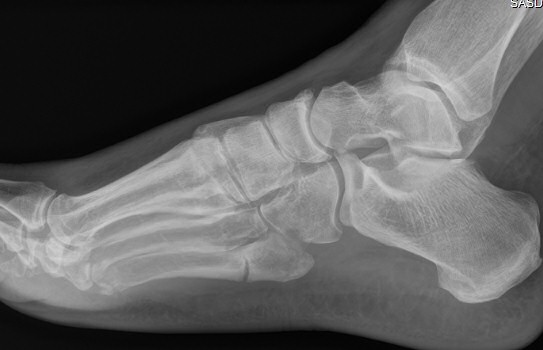

Mellan de röda strecken: ungefärligt läge för Jones-fraktur. Längre proximalt: avulsionsfraktur.

Exempel på Jones-frakturer, första bilden färsk, andra bilden ej läkt, tredje bilden efter operation.